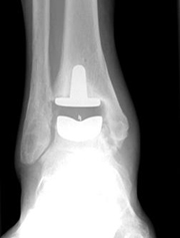

La prótesis se utiliza para sustituir una articulación que no funciona. Las prótesis de cadera y de rodilla son muy utilizadas para tratar la artrosis. La prótesis de tobillo se usa para tratar la degeneración articular de tobillo.

La prótesis de tobillo está indicada cuando la articulación del tobillo no puede seguir realizando su función de movimiento. Cuando pasa esto, las alternativas son fijar la articulación o colocar una prótesis. La ventaja de la prótesis es que se conserva el movimiento. Nuestros especialistas analizarán su caso y le aconsejarán si la prótesis de tobillo es la mejor solución.